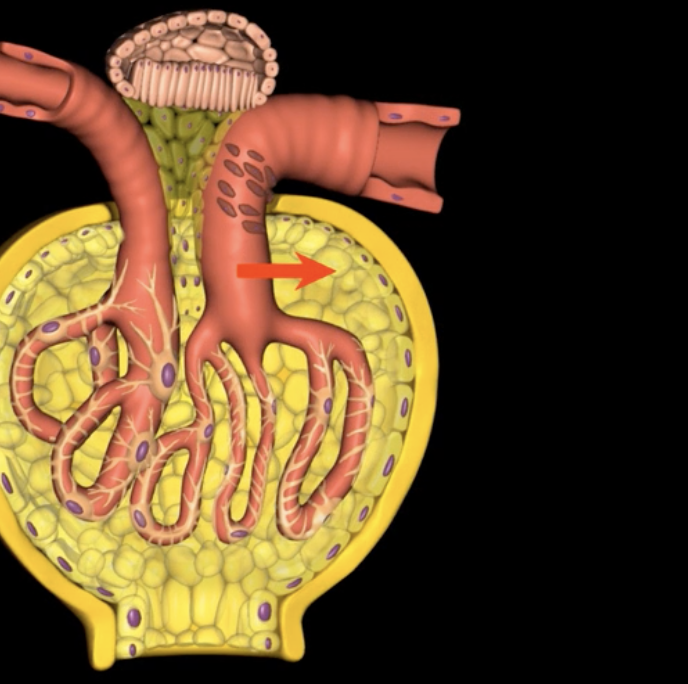

afferent arteriole

yellow

glomerulus

green

efferent arteriole

purple

orange: peritubular capillaries

green: vasa recta

efferent arteriole give rise to orange and green